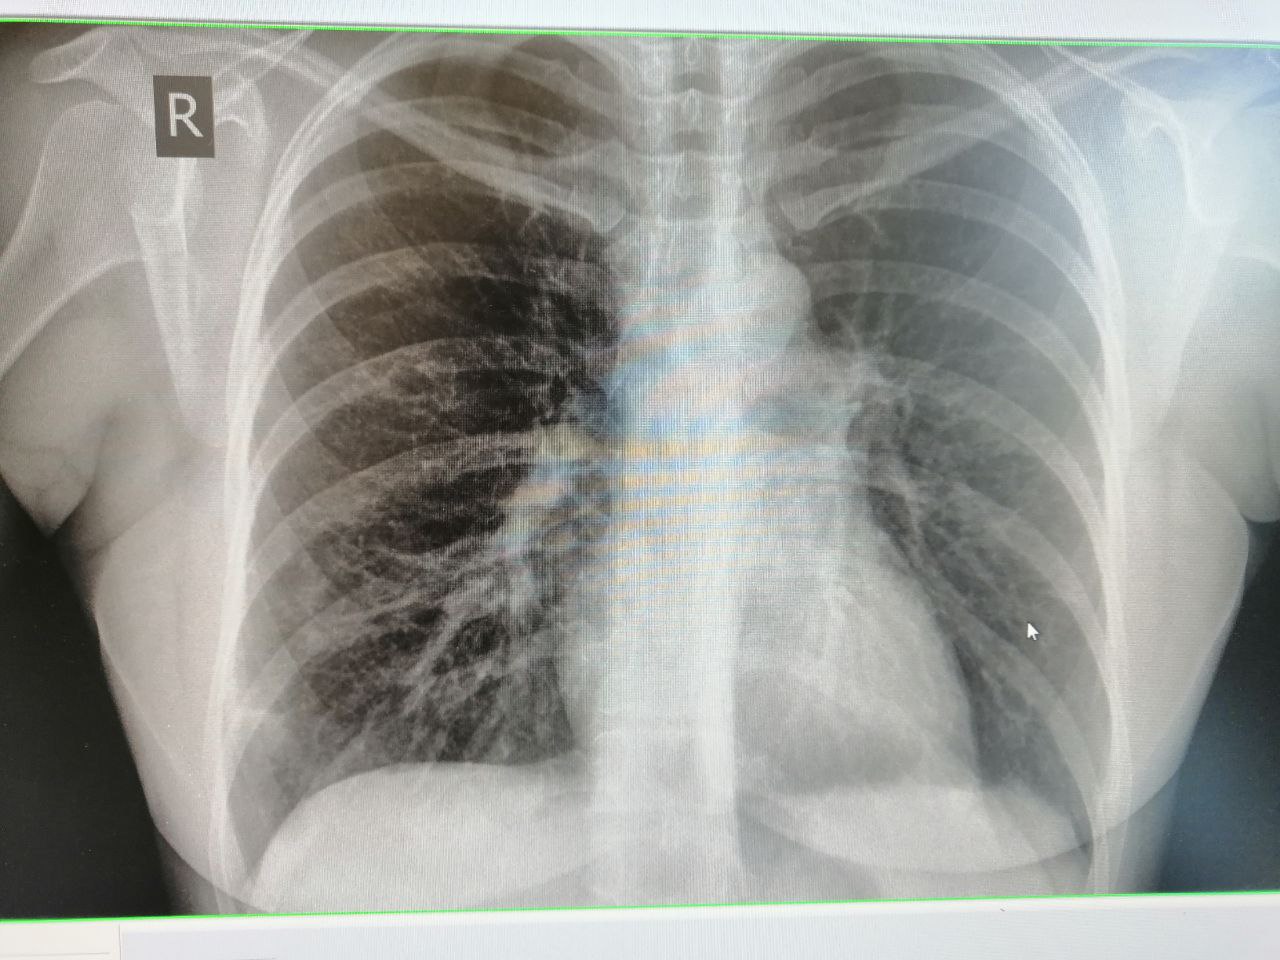

Не нравится внизу справа. Или все же норма?

справа по ходу паракостальной плеевры имеется инфильтративные изменения легочной ткани.

Правая грудь в норме? по возможности снимите правый боковой снимок

Этот участок не нравится

Есть только задняя проекция

тогда отправьте на кт

правая грудь уплотнена и инфильтрация сохраняется